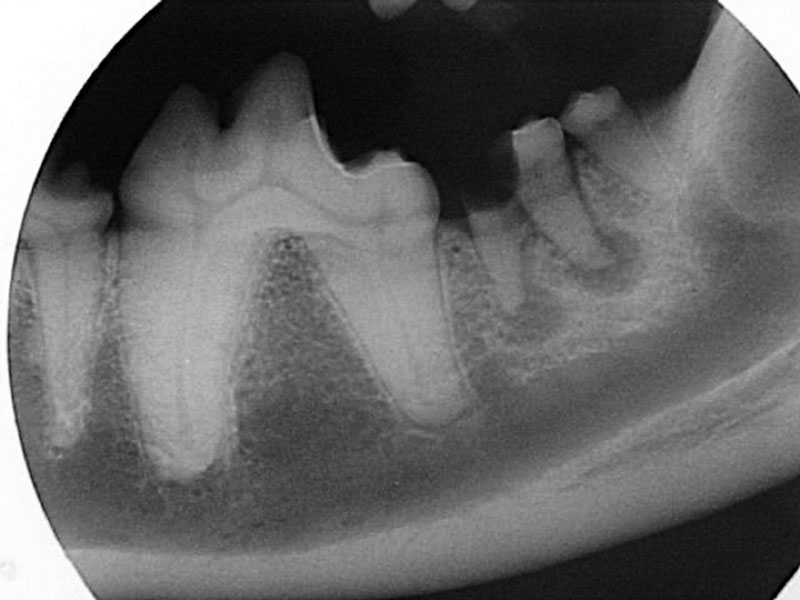

Radiograph of a severe caries lesion of the left mandibular second molar (tooth 310). The degree of crown loss is significant, and the caries bacteria have extended into the endodontic system, resulting in endodontic infection at the apices of the roots.

Figure 2: Radiograph of a severe caries lesion of the left mandibular second molar (tooth 310). The degree of crown loss is significant, and the caries bacteria have extended into the endodontic system, resulting in endodontic infection at the apices of the roots.

In dogs, the teeth most commonly affected by caries are the maxillary first molars (Figure 1), and when caries occur, the lesions are often bilateral. Feline caries lesions are more difficult to characterize because they are so rare. There are no prevalence studies of caries in cats, but there is one study that describes caries lesions in two 13th century cats from archived mandibles at an archeological museum.3 The lesions described in the manuscript were so small that they were radiographically undetectable, and these lesions were diagnosed with histologic stains and a test called the Knoop hardness test. In general, if a hard-tissue defect is found on the surface of a cat tooth, chances are that this is due to external tooth resorption. However, over the past 15 years, I have seen two cases of possible feline caries that were unlikely to be due to other more common causes, such as external or internal tooth resorption. Both of these lesions were arising in the lingual groove of the crown of the mandibular first molar tooth and had a radiographic appearance of an almost perfectly circular lucency isolated to the crown with no evidence of root resorption. Early caries lesions are not usually radiographically visible, but radiographic appearance of advanced caries show a circular loss of hard tissue arising from a central starting point, the central point often being an occlusal surface (Figure 2).